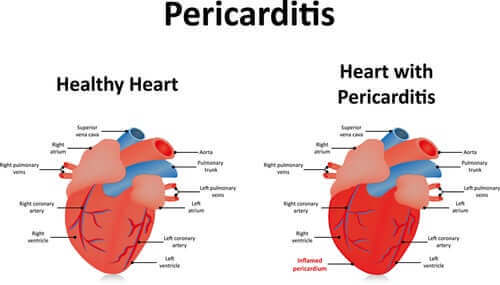

오늘은 심낭염의 증상, 원인 및 치료에 대해 알아본다. 심낭염(Pericarditis)은 심장을 둘러싸고 있는 주머니 모양의 막인 심낭의 염증을 말한다. 이 막은 두 개의 층과 그 사이에 있고 소량의 액체를 함유하고 있는데, 이는 두 층이 앞뒤로 미끄러지는 윤활제다. 사람의 체액이 많아지면 심낭염에 걸리게 된다.

심낭에 염증이 생기면 심장을 막히게 하고 그 기능을 손상할 수 있다. 하지만 대부분의 경우 큰 문제가 없고 치료도 받지 않고 가버리는 경우가 많다. 하지만, 가장 심각한 경우에는 약물치료와 심지어 수술까지 필요로 한다는 것을 유념하는 것이 중요하다.